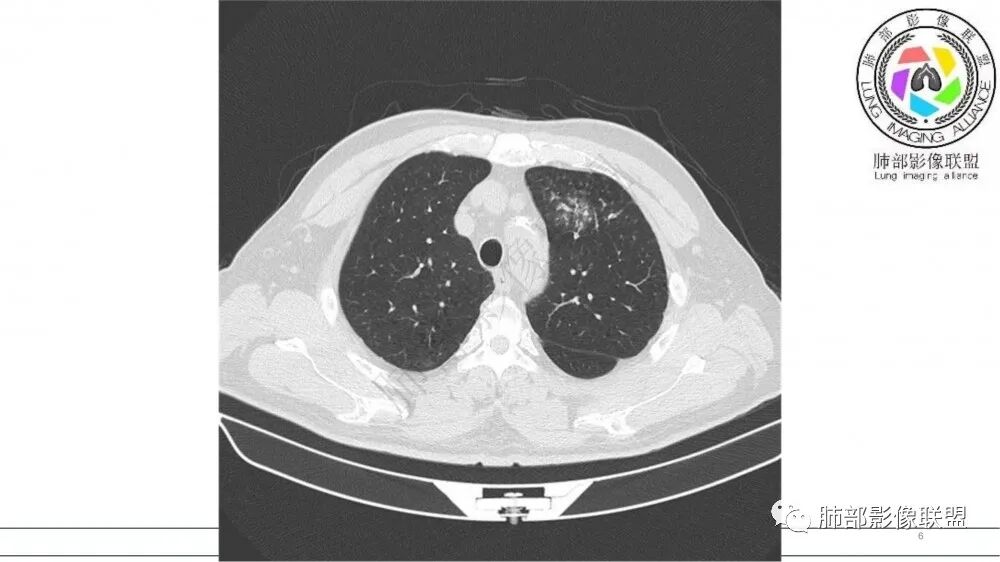

猜个鳞,沿支气管塑型生长,周围小花小草,肺门及纵隔淋巴结增大,吸烟老年男。鉴别TB

左肺上叶前段支气管杵状指样扩张,内见实性组织阻塞性,并强化明显,边缘饱满,周边多发小斑点影,小花小草征,老年男性,长期吸烟史,方向恶性,首选支气管内浸润鳞Ca可能性大。

男,70岁,吸烟史,咳嗽,胸闷憋气一个月,左肺上叶不规则形软组织密度影,病灶沿支气管走形,周围见粟粒及棉絮样稍高密度影,增强扫描病灶内见少许坏死,考虑鳞癌可能,鉴别结核。

老年男性,肺气肿,吸烟史,左肺上支气管腔内铸型高密度影,呈指套状,远端多发树芽,增强不均匀强化,考虑鳞癌,鉴别小细胞癌

小花小草,支气管阻塞,考虑鳞癌,鉴别腺癌,结核,及淋巴瘤

老年吸烟男,左肺上叶支气管堵塞,远端小花小草,纵隔未见肿大淋巴结,考虑鳞癌,建议进一步支气管镜检查

老年男性,长期吸烟史。左上肺前段沿支气管走形的指套样病变,增强可见病灶强化(排除结核、ABPA(也无气喘症状)),远端多发点状高密度影。考虑恶性肿瘤,鳞癌可能性大。

指套征,扩张支气管内软组织强化,远侧肺野阻塞性炎,纵隔、左肺门肿大淋巴结;老年男性,吸烟,考虑鳞癌,鉴别小

老年吸烟男性,尖前段支气管内塑形生长,增粗蠕虫样,没有肺不张(排除鳞癌?),远端少许阻塞肺炎,增强低强化,锁定小

老年男性,吸烟,指套征,蠕虫征,阻塞性炎症不严重。可见血管穿行,密度均匀,轻度强化,首先考虑小细胞肺癌。鉴别鳞

2021年8月6日晨读病例结果:小细胞肺癌

指套征:是影像征象,胸部平片表现为手指状密度增高影,以肺门为中心呈放射状分布,CT显示扩张支气管内低密度黏液栓形成或实性病变,呈管状、树枝状或卵圆形密度增高影;支气管扩张伴近端梗阻时,扩张支气管内部黏液分泌物不能排出而形成。可以伴随远端空气潴留征、阻塞性炎症。

研究报道,中心型 SCLC 经 CT 扫描后通常支气管表现为鼠尾样狭窄,肺门或纵隔肿块明显,由于肿块沿管壁生长表现为顺延支气管形态的不规则形状。病灶相对特征性影像学表现比如鸭蹼状、腊肠状、葫芦状及葡萄状改变,可以出现血管包埋,很少有空洞、空泡,较少引发肺不张,阻塞性炎症成都较轻。与一般肺癌比较,恶性程度高,侵袭力强、病灶很小就容易远处转移!Herzberg 等[19]研究指出,20%以上 SCLC 倍增时间短,预后不良。